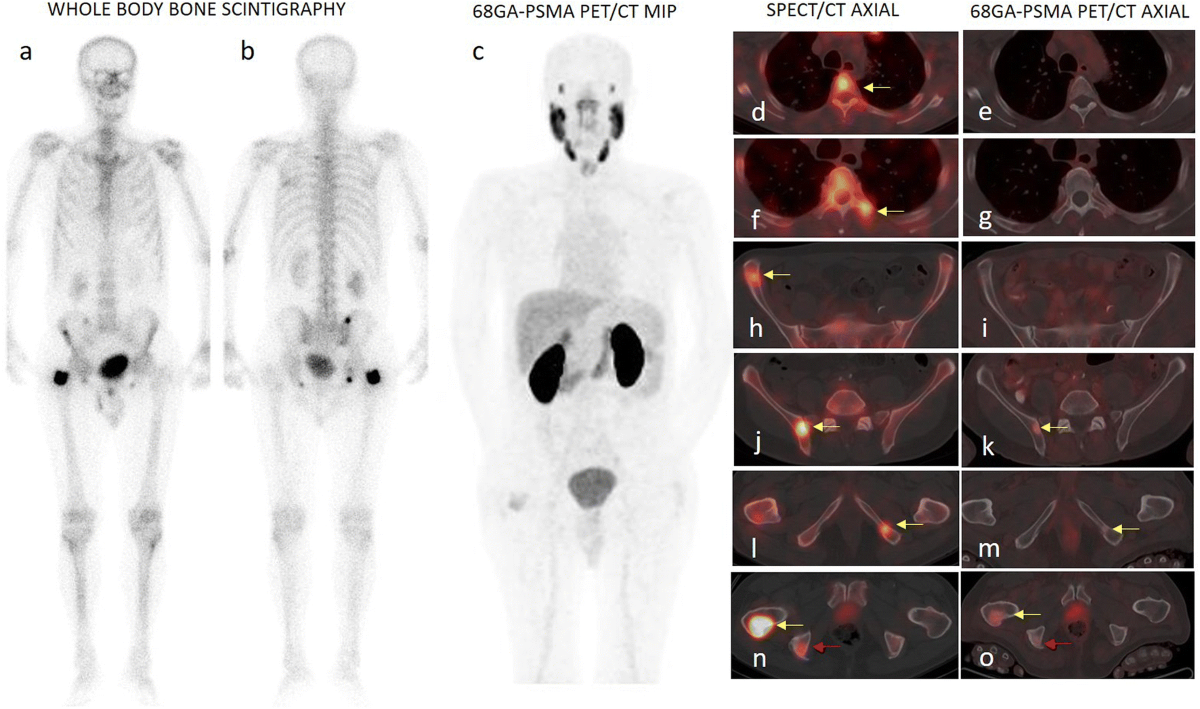

Comparison between 68Ga-PSMA PET and bone scintigraphy for skeletal staging in prostate cancer | Journal of Nuclear Medicine

image size: 1280x1189